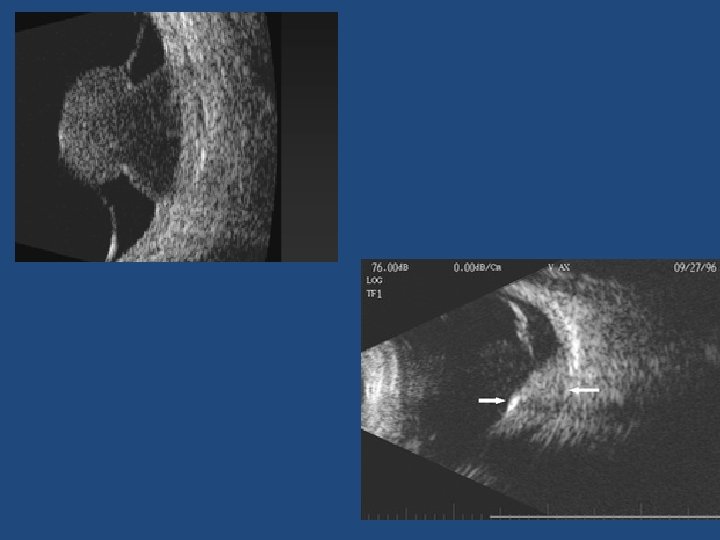

Other risk factors • Ultrasonographic hollowness • Thickness > 1. 5 mm • Suspicious OCT findings (p<0. 001)

Suspicious OCT findings • • • Intra retinal oedema Shaggy photoreceptors Loss of ELM Loss of IS/OS junction (p=0. 003) (p=0. 005) (p=0. 008) (p=0. 02)

Ultrasound vs OCT-EDI • OCT-EDI measurements are approximately 50% less thick than USB measurements (i. e. a 3 mm lesion on USB will measure 1. 5 mm on OCT-EDI) • USB cannot detect/measure lesions <0. 75 mm thick – these can be measured with OCT-EDI • OCT-EDI less helpful as tumours enlarge (>3 mm) • The lesion must be at least 1. 5 mm thick on USB measurement before meaningful comments on echogenicity can be made • USB echogenicity is determined by the density of cellularity of the tissue comprising the lesion (the denser the tissue the lesser the internal reflectivity) • OCT-EDI appearance is determined by the amount of pigment in the lesion and does not correlate to ultrasonic internal reflectivity • OCT-EDI offers a better estimate of the true dimensions of the lesion compared to USB